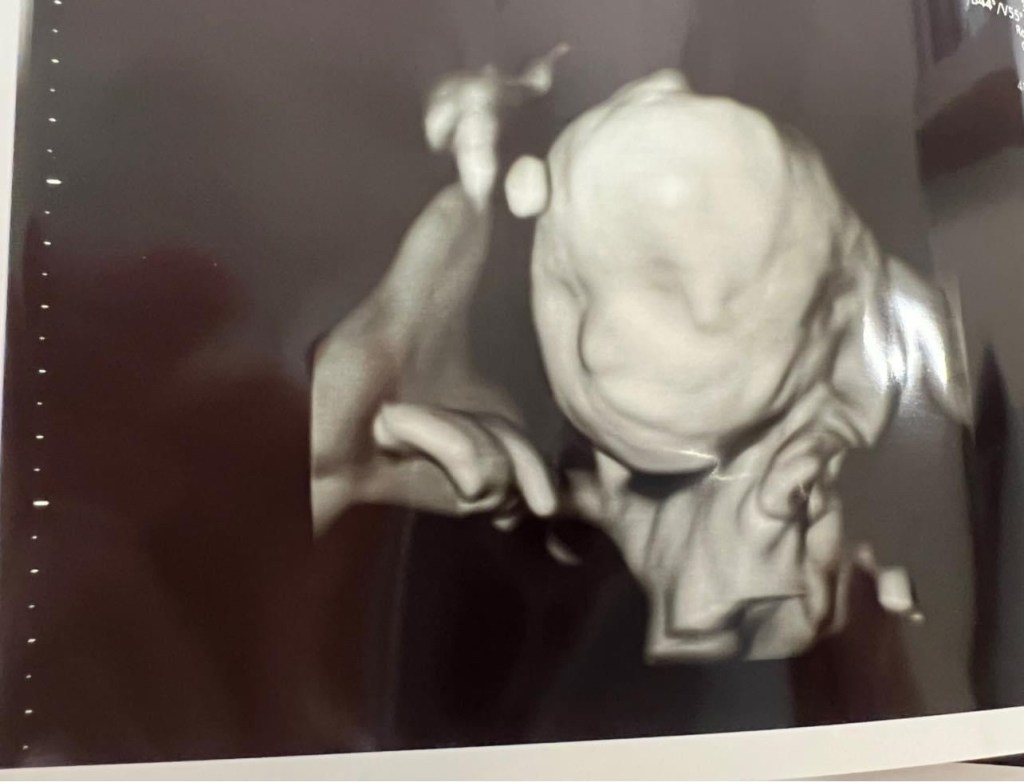

Amelia lived 38 weeks, 5 days in my womb and she lived 11 days after she was born. We are forever changed for having known and loved her.